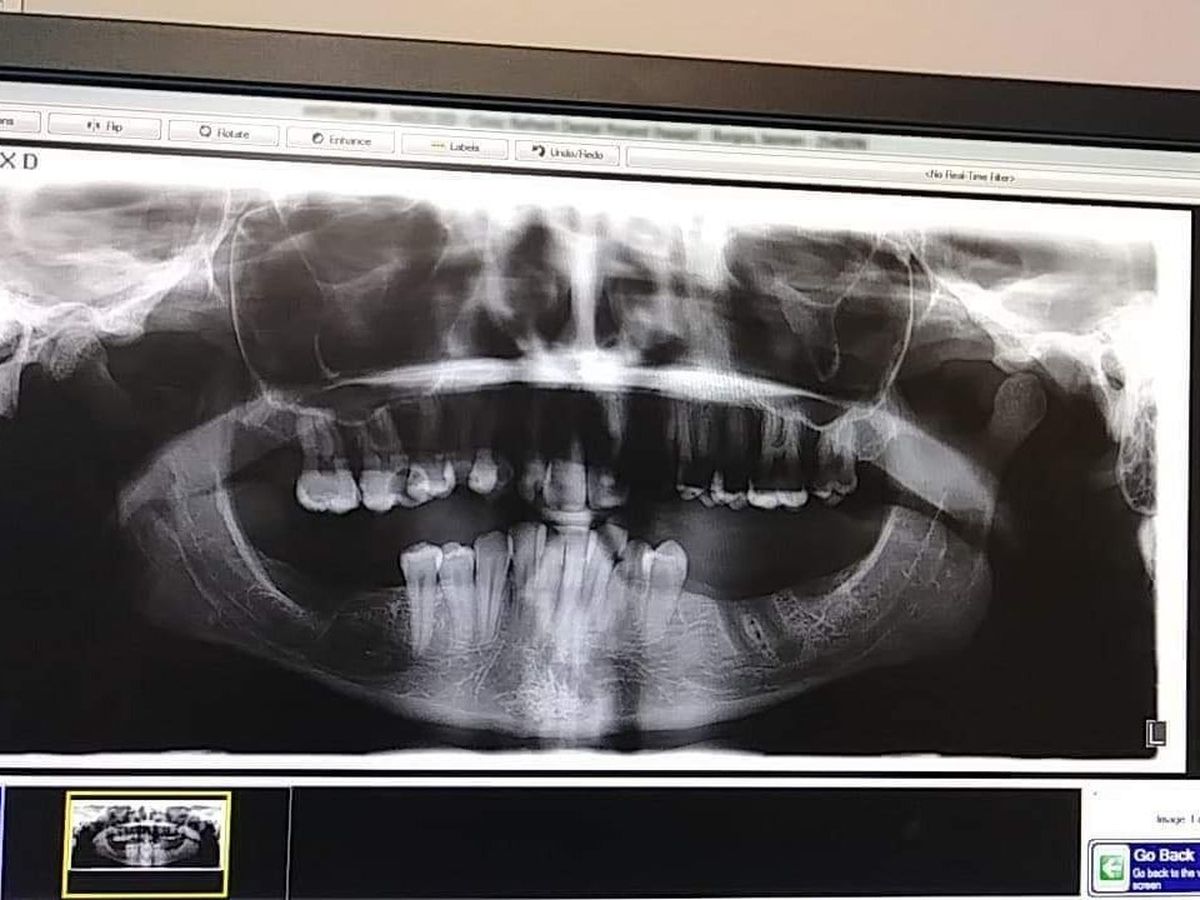

I need all my top teeth removed its covered. I need bonegrafting and healing dentures that is not. With 6 kids I cant pull funds from bills or their needs to do this. If I could have done it at a younger age I would have. Now I have time just not the money. if you can help thank you so much. Please no ride or negative comments. Ive been trying to get this done for many years. Ive been consumed by life completely and now I just need it done